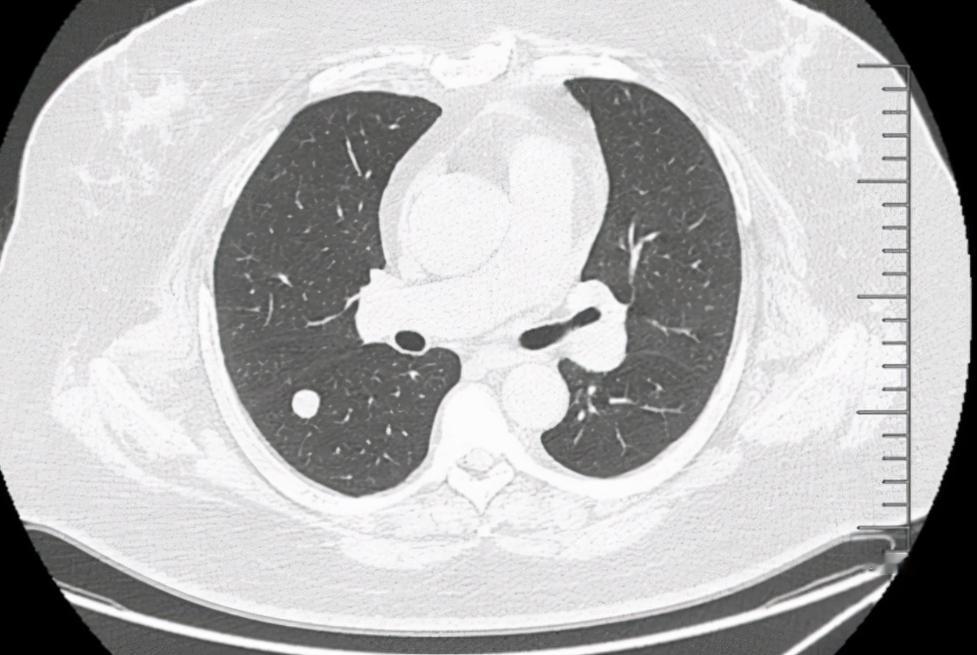

体检发现结节?这5种天然“散结小食材”,建议常吃 体检查出结节,确实会让人心里一紧。甲状腺、乳腺、肺部……这些部位长点“小疙瘩”,听起来吓人,但实际上,绝大多数都是良性的,只要按时复查、不要过度紧张。 除了按照医生建议监测,我们在日常饮食中,也可以适当选择一些有助于调理体质、化痰散结、维持内环境平衡的天然食材,今天就给大家推荐5种日常常见的“散结”食材,平时可以适量吃一些: 1. 山药 山药被称为“脾胃的朋友”。中医认为脾运好,痰湿就不容易积;反之痰多、气滞,就容易形成结节。山药有健脾、益气、化湿的作用,适合胃口差、有痰湿体质的人作为日常调理。 2. 绿叶蔬菜(菠菜、生菜、小白菜等) 绿叶蔬菜营养丰富,含有丰富的维生素和矿物质,同时具有清热解毒、促进代谢的作用。经常吃绿叶菜,有助于维持身体内环境的平衡,让结节不易发展。 3. 青木瓜 青木瓜富含植物酶,能帮助胃肠消化,也有疏肝、软坚、化滞的作用。 很多结节与情绪不畅、肝气郁滞有关,青木瓜温和开郁,是不错的日常选择。 4. 莲藕 莲藕性平味甘,既能润肺、也能活血散瘀。很多结节与轻度瘀血、气机不通有关,常吃一点莲藕,有助于:促进局部循环,调畅气血,,缓解气滞型不适 5. 柠檬水 柠檬富含维C和天然抗氧化物质,可帮助清除自由基、支持免疫系统稳定运行。 从中医讲,柠檬偏酸,能生津、疏肝,适合紧张、易焦虑、乳腺容易胀痛的人。️ 温馨提醒:食疗只能作为辅助调理,不能替代正规的医学检查和治疗。发现结节后,请一定遵医嘱复查,同时保持好心态、合理作息、健康生活方式! 中医结节肺结节[超话]乳腺结节